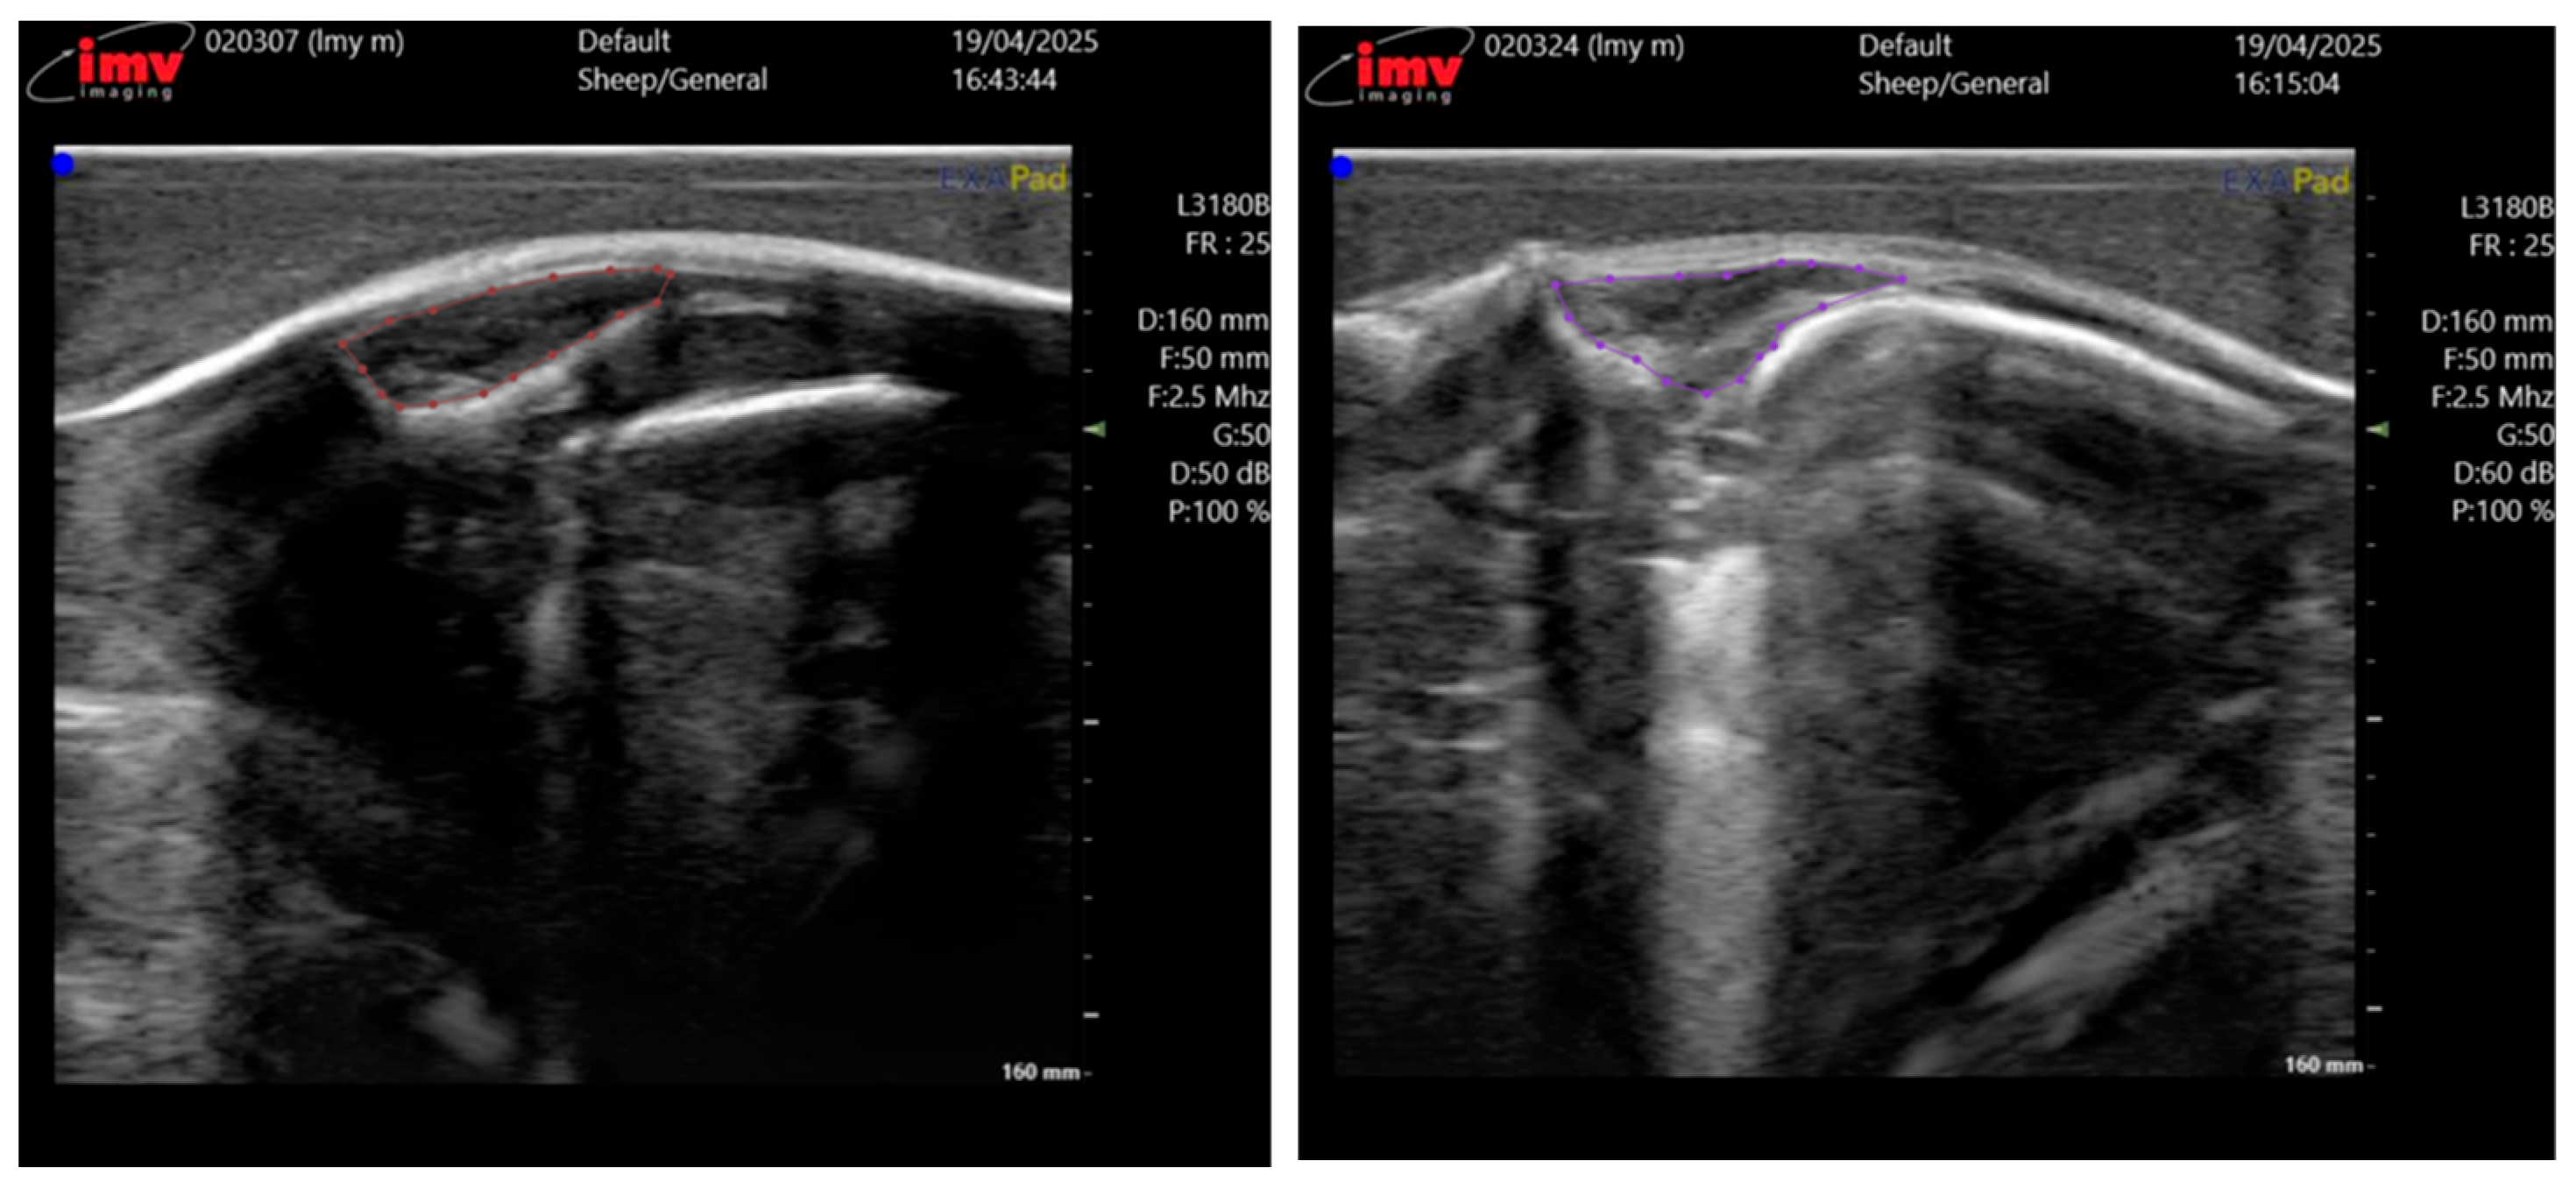

The ultrasound images were acquired by two professional technicians. Both operators were strictly trained to follow the same standard scanning procedure to minimize inter-operator variability. The collected data is uniformly stored and transmitted on the hard drive. We collected ultrasound images from a total of 230 Taonan Lake hybrid sheep, all of which were less than 12 months old, amounting to 710 images, each with a resolution of 730 × 660 pixels. These images were randomly split into training, validation, and test sets at a 7:2:1 ratio, forming the dataset for our eye muscle segmentation experiments. The entire data annotation was performed in a two-stage process to ensure accuracy. First, doctoral students specializing in animal science, trained in ultrasound anatomy, used the LabelMe software 3.16.2 to delineate the eye muscle regions in all 710 images. Subsequently, the annotations were rigorously reviewed and corrected by technical specialists from the device manufacturer and chief domain experts, each possessing over 20 years of research experience in sheep breeding and livestock husbandry, to serve as the ground truth. Figure 2 illustrates the annotation results for two representative meat sheep.

Figure 2. Annotation results for sheep eye muscle ultrasound images. The circled area corresponds to the region of the EMA.